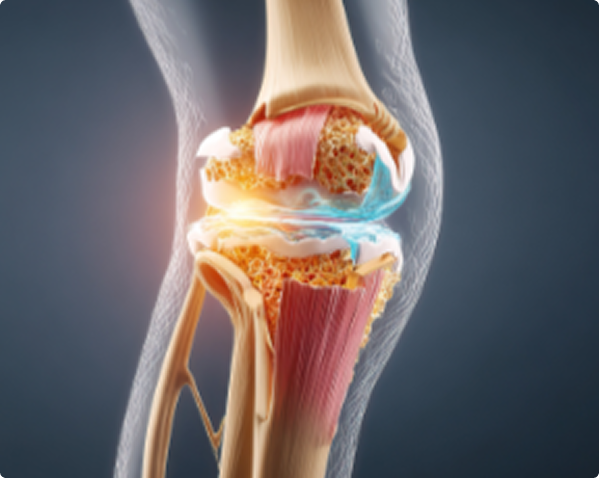

What Causes Knee Pain?

Osteoarthritis occurs when the protective cartilage in your knee gradually breaks down. This leads to inflammation in the joint lining, resulting in:

How Does GAE Work?

During the procedure, a small catheter is guided into the arteries supplying the knee. Tiny particles are then used to reduce blood flow to inflamed tissue.

By decreasing inflammation, GAE helps: